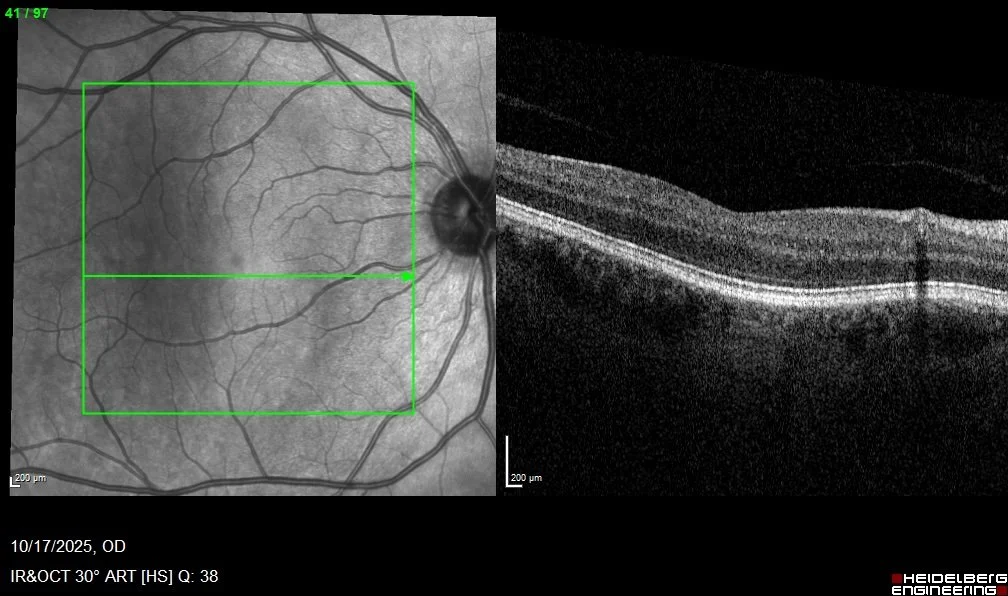

2. Elite Imaging: Our technicians capture Ultra-Widefield Fundus Photos and Macular OCT (cross-sectional imaging).